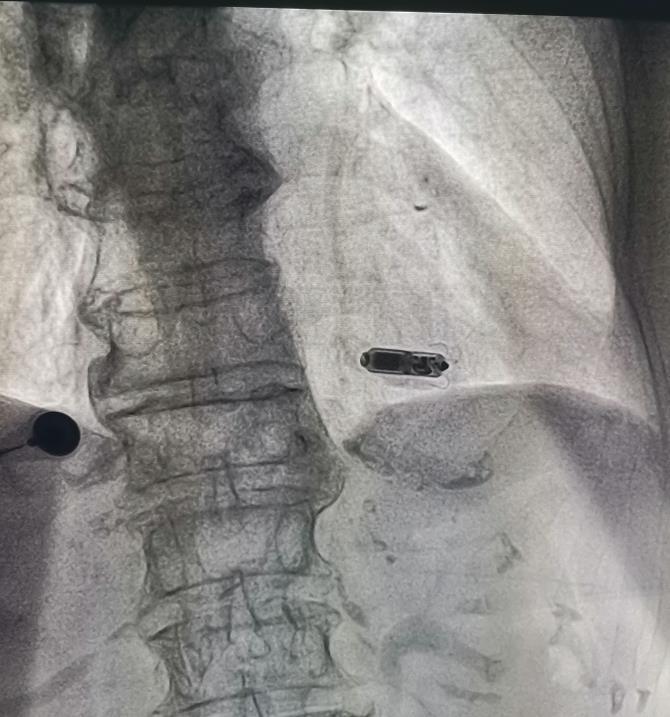

8月6日上午 , 在成都五医院麻醉科及介入室的全力配合 , 四川大学华西医院心内科指导下 , 成都五医院心内科起搏团队成功将起搏器通过导管植入到刘奶奶右心室室间隔中下部 。 手术顺利 , 用时仅22分钟 。 术后 , 刘奶奶心跳恢复到了每分钟60次 , 并且几乎感觉不到起搏器的存在 。 术后恢复良好 , 并在8月9日出院 。

郎主任介绍道 , Micra虽然小 , 但是寿命却长达12年以上 , 同时还能够兼容3.0T核磁共振扫描检查 , 可为心脏提供持续稳定的动能 , 大大提高患者的生活质量 。